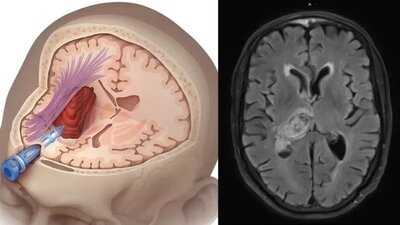

Brain Stroke: जब मस्तिष्क की कोई नस ब्लॉक हो जाती है तो ब्रेन स्ट्रोक होता है। यह जानलेवा स्थिति है जिसका समय पर इलाज न मिलने पर मौत भी हो सकती है। लेकिन क्या आप मिनी ब्रेन स्ट्रोक के बारे में जानते हैं?

जो किसी बड़े अटैक से बहुत पहले ही सामने आ सकता है। इसके लक्षण हल्के होते हैं जिन्हें समय रहते पहचानकर बड़े अटैक से बचा जा सकता है। इसे मिनी ब्रेन स्ट्रोक या ट्रांसिएंट इस्केमिक अटैक भी कहते हैं।

ब्रेन स्ट्रोक की तरह ही छोटा ब्रेन अटैक भी दिमाग की किसी नस के ब्लॉक होने की वजह से होता है। NHS (ref.) के मुताबिक इसकी वजह से दिमाग को ऑक्सीजन मिलना बंद हो जाता है। लेकिन यह नुकसान स्थायी नहीं होता और 24 घंटे के अंदर अपने आप ठीक हो जाता है। लेकिन इसके लक्षणों को हल्के में नहीं लेना चाहिए और डॉक्टर से सलाह लेनी चाहिए।